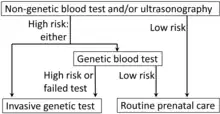

Guidelines recommend screening for Down syndrome to be offered to all pregnant women, regardless of age.[100][101] A number of tests are used, with varying levels of accuracy. They are typically used in combination to increase the detection rate.[28] None can be definitive, thus if screening is positive, either amniocentesis or chorionic villus sampling is required to confirm the diagnosis.[100]

When screening tests predict a high possibility of Down syndrome, a more invasive diagnostic test (amniocentesis or chorionic villus sampling) is needed to confirm the diagnosis.[100]

Combinations

| Screen | Week of pregnancy when performed | Detection rate | False positive | Description |

|---|---|---|---|---|

| Combined test | 10–13.5 wks | 82–87% | 5% | Uses ultrasound to measure nuchal translucency in addition to blood tests for free or total beta-hCG and PAPP-A |

| Quad screen | 15–20 wks | 81% | 5% | Measures the maternal serum alpha-fetoprotein, unconjugated estriol, hCG, and inhibin-A |

| Integrated test | 15–20 wks | 94–96% | 5% | Is a combination of the quad screen, PAPP-A, and NT |

| Cell-free fetal DNA | From 10 wks[109] | 96–100%[106] | 0.3%[110] | A blood sample is taken from the mother by venipuncture and is sent for DNA analysis. |

Efficacy

For combinations of ultrasonography and non-genetic blood tests, screening in both the first and second trimesters is better than just screening in the first trimester.[100] The different screening techniques in use are able to pick up 90–95% of cases, with a false-positive rate of 2–5%.[104] If Down syndrome occurs in one in 500 pregnancies with a 90% detection rate and the test used has a 5% false-positive rate, this means, of 20 women who test positive on screening, only one will not have a fetus with Down syndrome confirmed.[104] If the screening test has a 2% false-positive rate, this means, of 50 women who test positive on screening, one will not have a fetus with Down syndrome.[104]

Invasive genetic testing

Amniocentesis and chorionic villus sampling are more reliable tests, but they increase the risk of miscarriage by between 0.5-1%.[111] The risk of limb problems may be increased in the offspring if chorionic villus sampling is performed before 10 weeks.[111]

The risk from the procedure is greater the earlier it is performed, thus amniocentesis is not recommended before 15 weeks gestational age and chorionic villus sampling before 10 weeks gestational age.[111]